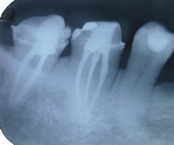

Here is an X-ray of two molars that have had root canal procedures. The root fillings are the white lines inside the roots, in the middle of each tooth. The tooth on the right of the picture is a normal tooth.